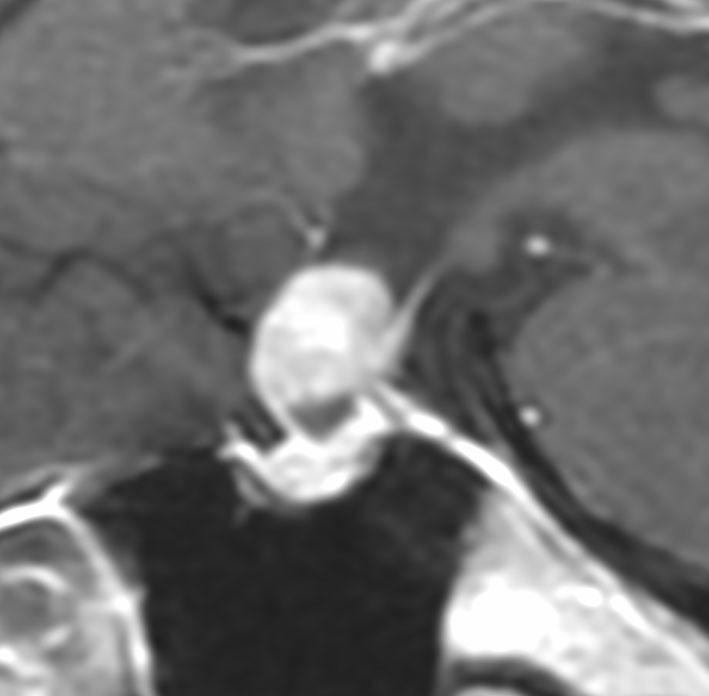

40代の女性に,軽度の両耳側半盲で発生したものです。視交叉と視床下部の下面に腫瘍があり,下垂体柄の位置が全くわからず,下垂体の前葉と後葉は侵されていません。ですから,下垂体柄から発生した腫瘍であり,pituicytomaが強く疑われます。T2ではほぼ等信号,小さなのう胞があり,ガドリニウムで強く増強されます。手術では正常下垂体柄の一部が右側にうすく残っており,幸運にも亜全摘出できて下垂体機能は温存できました。残存腫瘍は増大傾向を示していません。でも,このようなタイプを積極的に摘出すると,汎下垂体機能低下症を招くことが多いので,手術するかどうかの判断はとても難しいです。

この例は下垂体柄が認識できて,灰白隆起から発生したとしか思えませんでした

- 画像上は境界が明瞭な腫瘍です

- 腫瘍内部にvascular voidsが多く見えて激しく出血する腫瘍です

- トルコ鞍内から発生することが多いと記載されていますが,実際は灰白隆起か下垂体柄からの発生が多く,鞍上部腫瘍となります